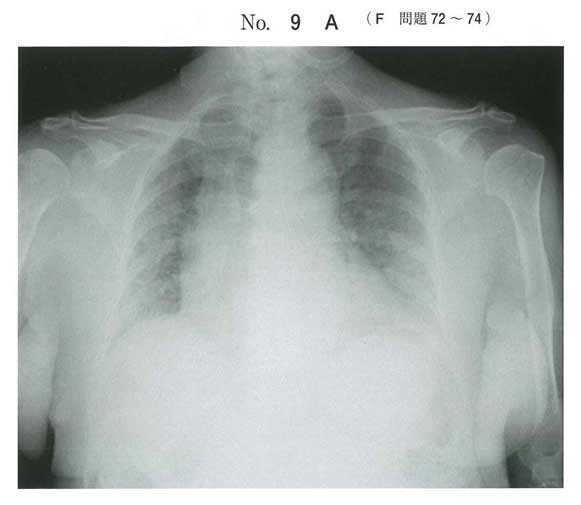

PCP

β-D-グルカン高値→真菌→グロコット染色

ステロイド使うときはニューモシスチス注意ですな